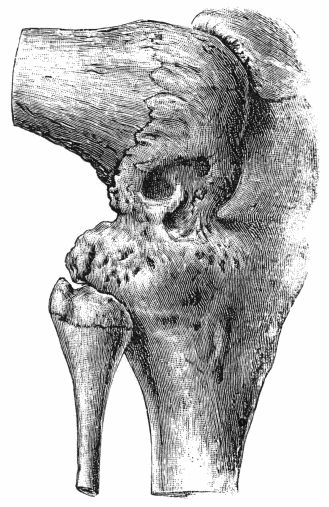

| 162. | Bones of Knee in Charcot's Disease | 533 |

| 163. | Charcot's Disease of Left Knee | 534 |